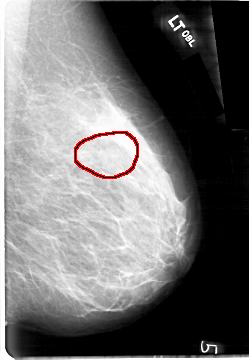

FILE: D_4092_1.LEFT_MLO.OVERLAY

TOTAL_ABNORMALITIES 1

ABNORMALITY 1

LESION_TYPE MASS SHAPE OVAL MARGINS OBSCURED

ASSESSMENT 0

SUBTLETY 4

PATHOLOGY BENIGN

TOTAL_OUTLINES 1

BOUNDARY